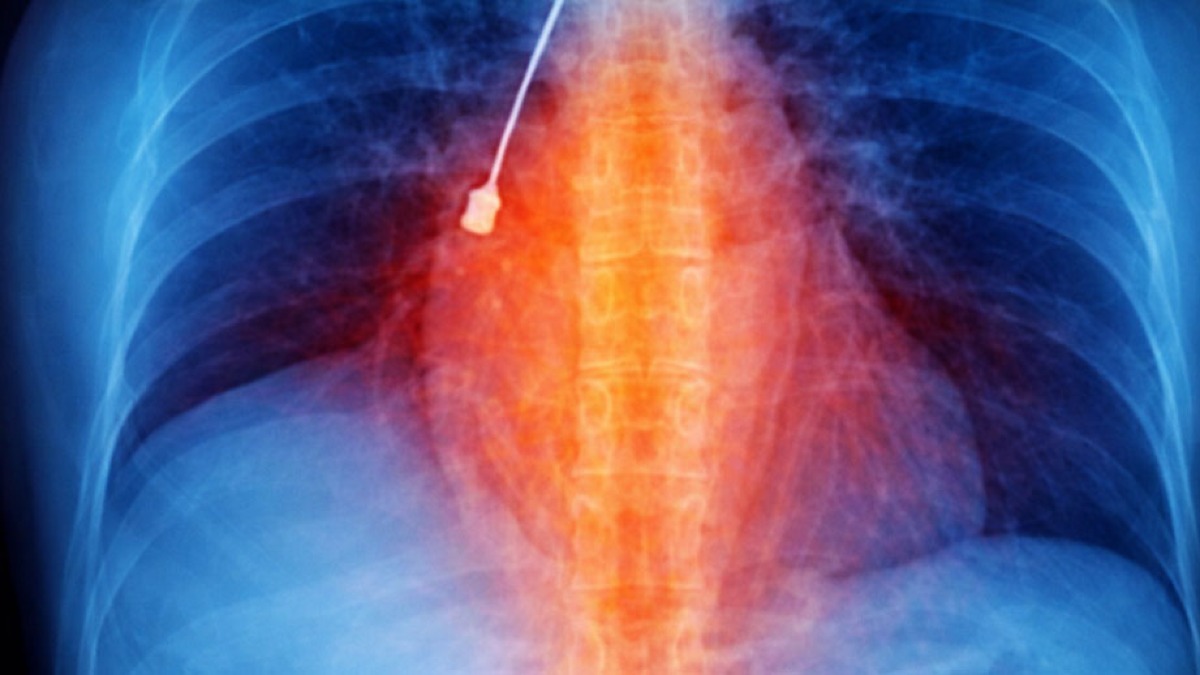

Un cacciavite odontoiatrico inalato accidentalmente e rimasto incastrato in un bronco polmonare. È la scoperta choc che ha portato una giovane donna al Pronto Soccorso del Grande Ospedale Metropolitano di Reggio Calabria, dopo giorni di tosse persistente e forti dolori toracici.

L’episodio si è verificato nelle scorse settimane. La paziente si è presentata in emergenza mostrando una Tomografia Computerizzata eseguita per chiarire l’origine dei sintomi. L’esame ha rivelato la presenza di un corpo estraneo metallico pericolosamente bloccato nel bronco lobare inferiore del polmone destro, associato a un pneumomediastino, una condizione caratterizzata dalla presenza di aria nello spazio tra i due polmoni.